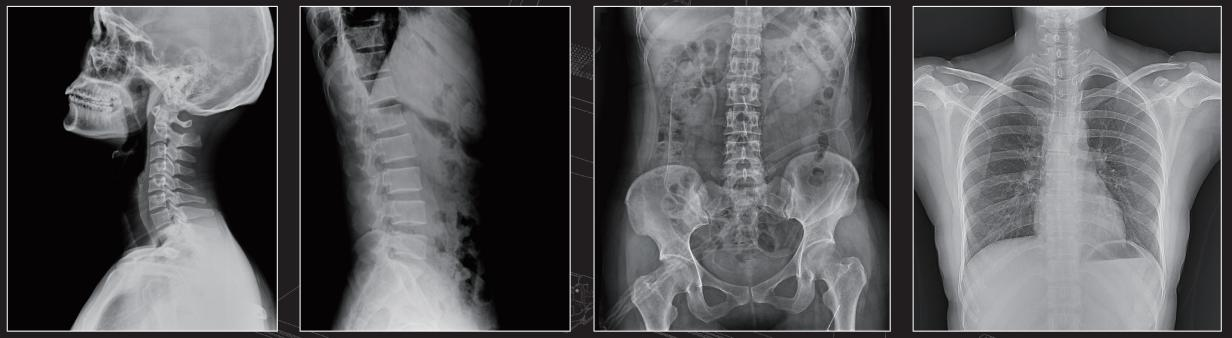

Ang MCI0402 digital X-ray machine kay versatile ug kasaligan, nagsuporta sa usa ka halapad nga han-ay sa mga klinikal nga aplikasyon. Gigamit kini alang sa komprehensibo nga imaging sa lain-laing mga bahin sa lawas, lakip na ang orthopedic evaluation, emergency diagnostics, ug naandan nga mga pamaagi sa screening. Kung alang sa chest X-ray, eksaminasyon sa taludtod, o pag-scan sa tiyan, kini nga sistema naghatag sa katukma ug kasaligan nga gikinahanglan alang sa tukma nga pagdayagnos.

Ang MCI0402 digital X-ray machine kay versatile ug kasaligan, nagsuporta sa usa ka halapad nga han-ay sa mga klinikal nga aplikasyon. Gigamit kini alang sa komprehensibo nga imaging sa lain-laing mga bahin sa lawas, lakip na ang orthopedic evaluation, emergency diagnostics, ug naandan nga mga pamaagi sa screening. Kung para sa X-ray sa dughan, eksaminasyon sa taludtod, o pag-scan sa tiyan, kini nga sistema naghatag sa katukma ug kasaligan nga gikinahanglan alang sa tukma nga pagdayagnos.